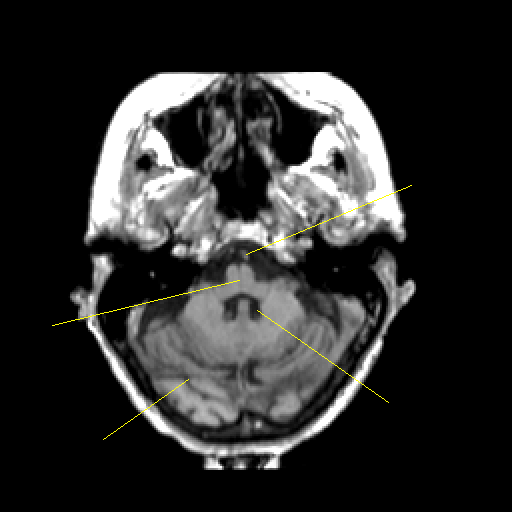

T1-weighted structural MR: Slice 12

Slice 12

Pointers

Labeled